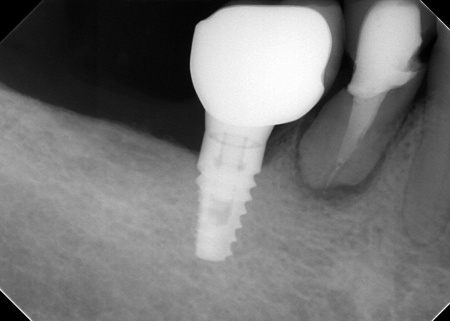

70代男性 右下奥歯を抜いてインプラント治療で噛み合わせを回復した症例

顎の骨に人工歯根を埋入し、その上から人工歯を装着する方法です。

まず、右下奥歯(第2小臼歯)を抜き、骨が治癒するのを待ってから、インプラントを埋入します。

インプラントと顎の骨がしっかりと結合したら、精密な型取りを行い、インプラント上部に装着する最終的な被せ物を作製しました。

最後に完成した被せ物を装着し、見た目や噛み合わせに問題がないことを確認して、治療を終了しています。